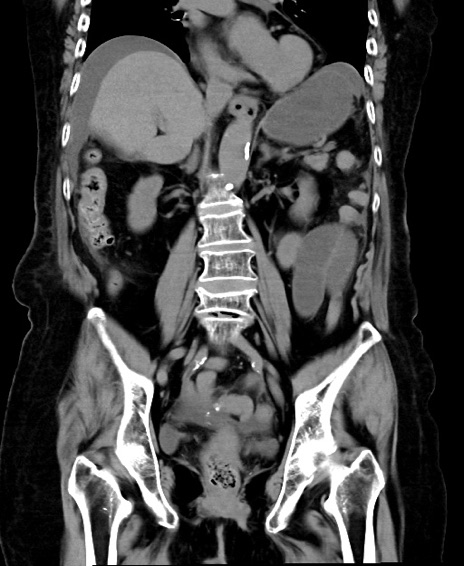

横断像

冠状断像